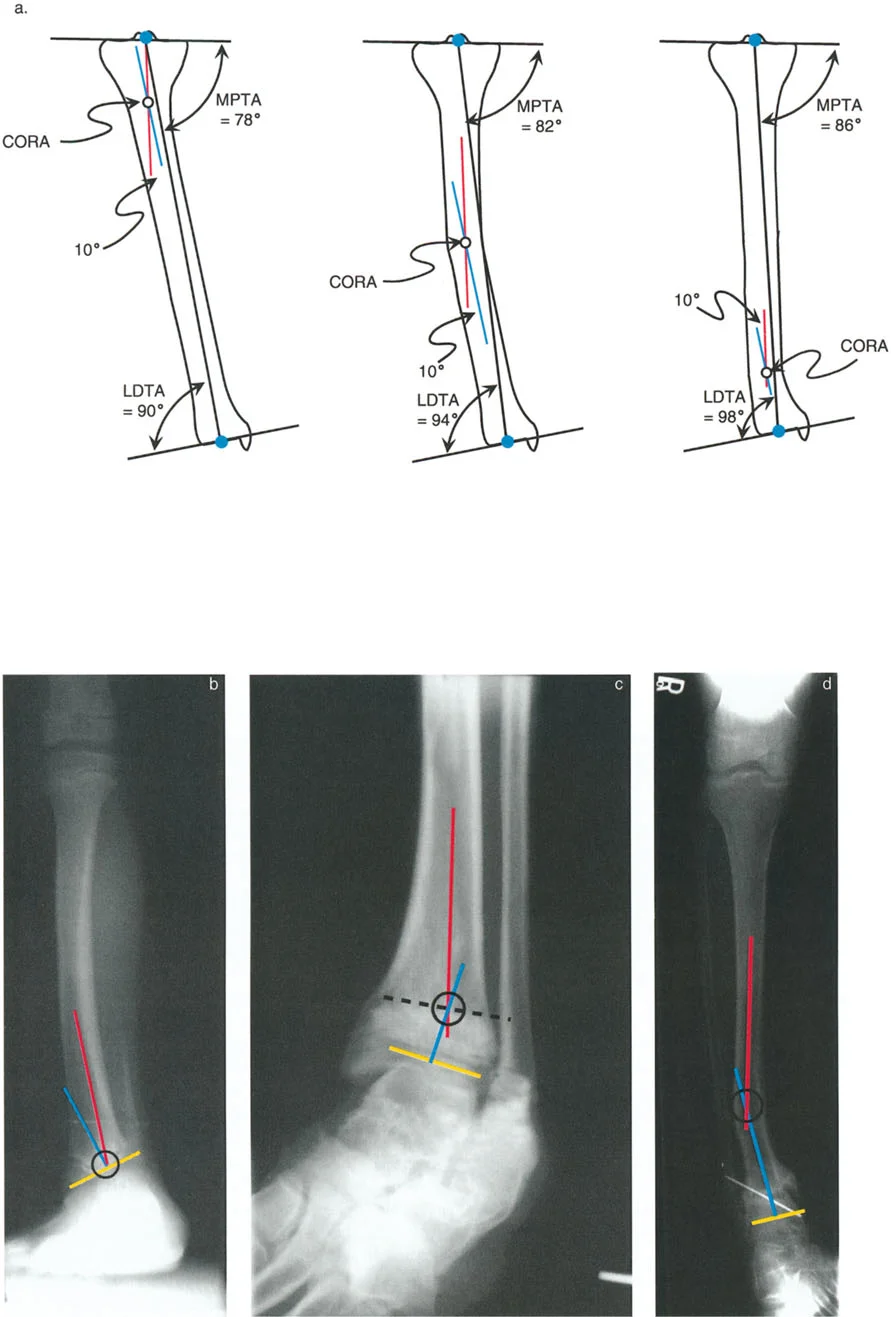

مبادئ بالي لتصحيح التشوهات

تُعد مبادئ الدكتور درور بالي حجر الزاوية في جراحة تصحيح تشوهات العظام. تركز هذه المبادئ على تحديد "مركز دوران التشوه" (CORA - Center of Rotation of Angulation) بدقة. إن موقع CORA يحدد كيفية تأثير التشوه على المفاصل المجاورة ويوجّه الجراح في اختيار مكان قطع العظم (Osteotomy).

• فهم CORA:

• إذا كان CORA قريبًا من مفصل الكاحل، فإن التشوه يؤثر بشكل أساسي على محاذاة الكاحل.

• إذا كان CORA قريبًا من مفصل الركبة، فإن التشوه يؤثر بشكل أساسي على محاذاة الركبة.

• إذا كان CORA في منتصف عظم الساق، فإنه يؤثر على كلا المفصلين ولكن بدرجة أقل.

• قواعد بالي لقطع العظم:

1. القاعدة الأولى: عندما يمر قطع العظم ومحور تصحيح الزاوية (ACA) عبر CORA، يتم تحقيق تصحيح زاوي نقي دون أي إزاحة.

2. القاعدة الثانية: عندما يمر ACA عبر CORA، ولكن قطع العظم يتم في مستوى مختلف (غالبًا ما يكون ضروريًا لتوفير مساحة كافية للتثبيت)، يتم تحقيق تصحيح زاوي نقي، ولكن أطراف العظم ستنزاح في موقع قطع العظم. يجب على الجراح توقع هذه الإزاحة وإدارتها.

3. القاعدة الثالثة: إذا كان ACA وقطع العظم في نفس المستوى، ولكن لا يمر أي منهما عبر CORA، فسيحدث تشوه إزاحة (ترجمة) غير مرغوب فيه. يتطلب هذا الأمر من الجراح إجراء إزاحة متعمدة للقطعة العظمية البعيدة أثناء التصحيح الزاوي لإعادة محاذاة المحور الميكانيكي.